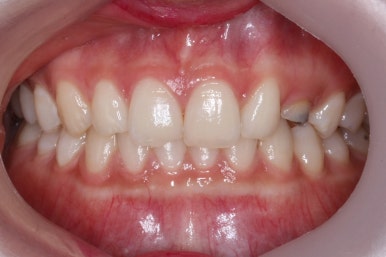

부산매복치아교정 상악 부분교정을 통해 매복치를 교정해준 이번 치료의 전후사진 비교입니다.

썩은 유치 대신 영구치 송곳니는 매우 자연스럽게 위치되었습니다. 아랫니는 교정하지 않았기 때문에 약간 삐뚠 느낌은 남아있지만 맞물림은 크게 문제가 없게 마무리 되었습니다.

얼굴 모습에서의 전후 비교입니다.

처음부터 매복치 이외에는 얼굴모습에서의 큰 문제가 없었고, 변화를 의도하지도 않았기 때문에 전후 모습의 큰 차이는 없습니다.

대신, 송곳니가 제위치되면서 웃거나 말할 때 미적으로 많이 개선된 것을 볼 수 있습니다.